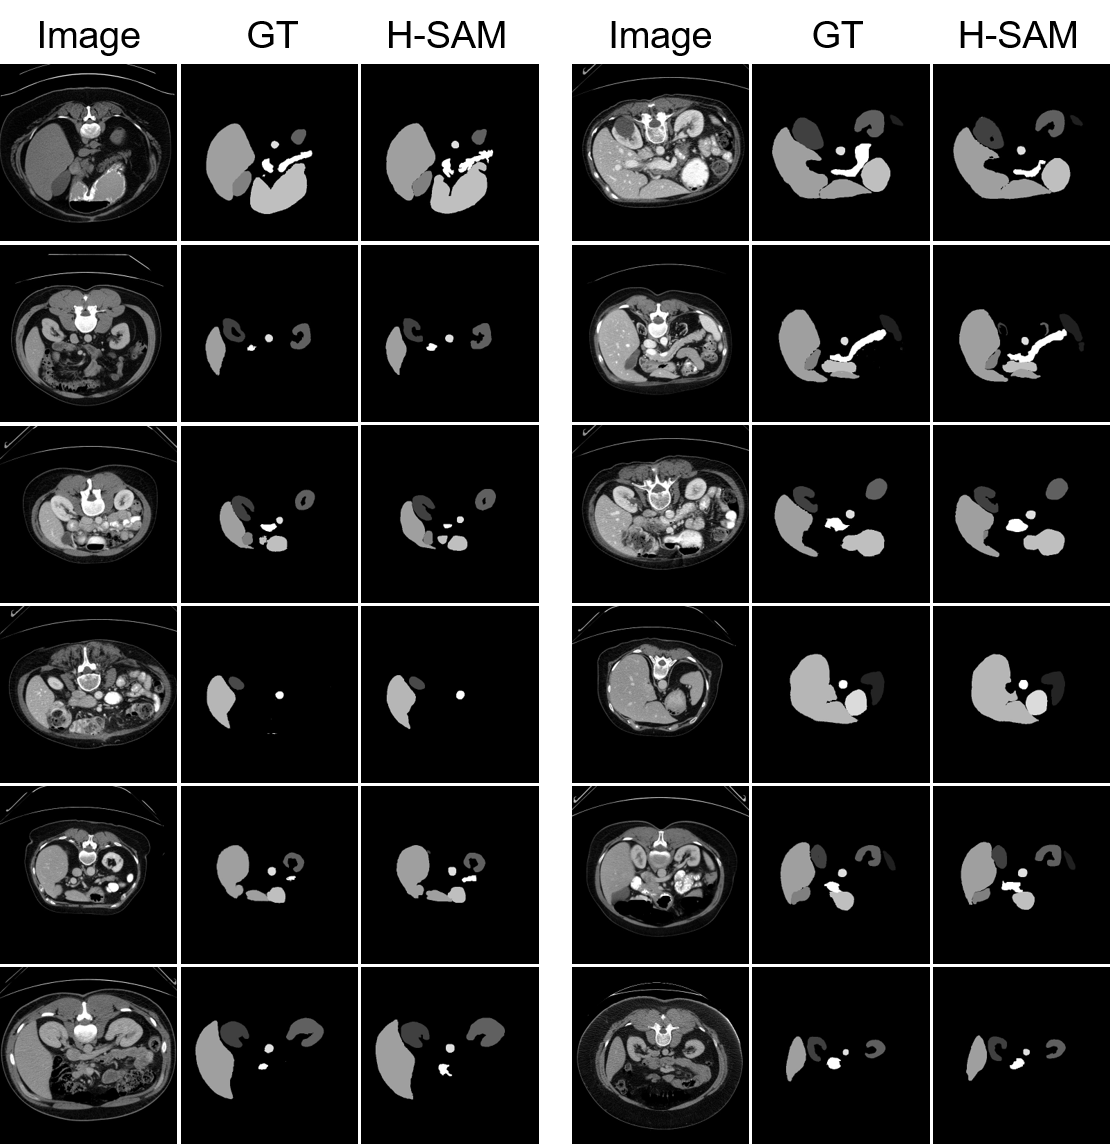

Refer to caption

Figure 5: The qualitative results of H-SAM and other SAM variants, including SAMed, SAM Adapter, and AutoSAM.

4.6 Qualitative Results

As shown in Figure 5, we compare our H-SAM to other prompt-free medical SAM variants, including AutoSAM [10], SAM Adapter [31] and SAMed [71]. As pointed out in the first row and the last row, compared to other SAM variants, H-SAM provides a precise mask prediction with lesser noise. In the second row, where other methods misrecognize Aorta and Pancreas to Stomach and Aorta, H-SAM provides correctly attributes each organ to their categories. H-SAM also performs superiorly with small-scale organs. In the third row, while all other variants miss Spleen, only H-SAM provides correct prediction for all of the organs.